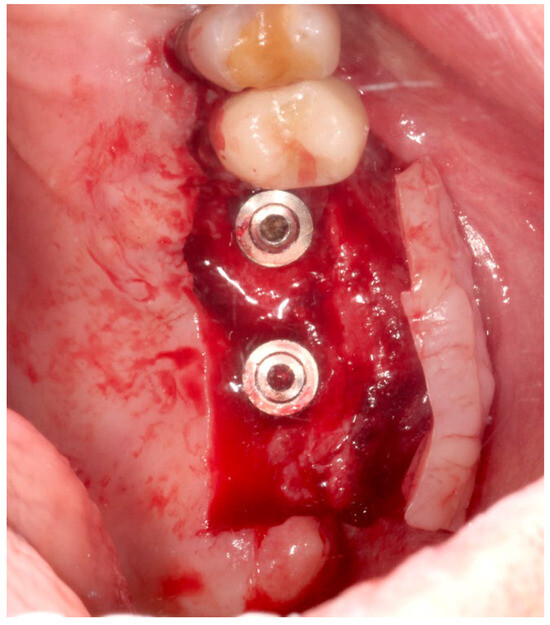

2.3. Surgical Procedure